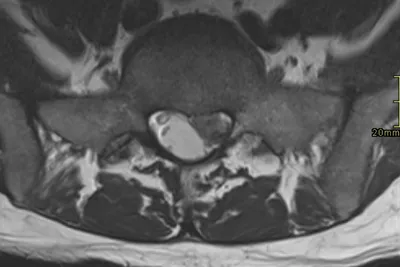

Extrusion Radiology Images

This collection contains 1 radiology images related to extrusion, including various imaging modalities such as X-rays, MRIs, CT scans, and ultrasound images commonly used in medical diagnosis and education.